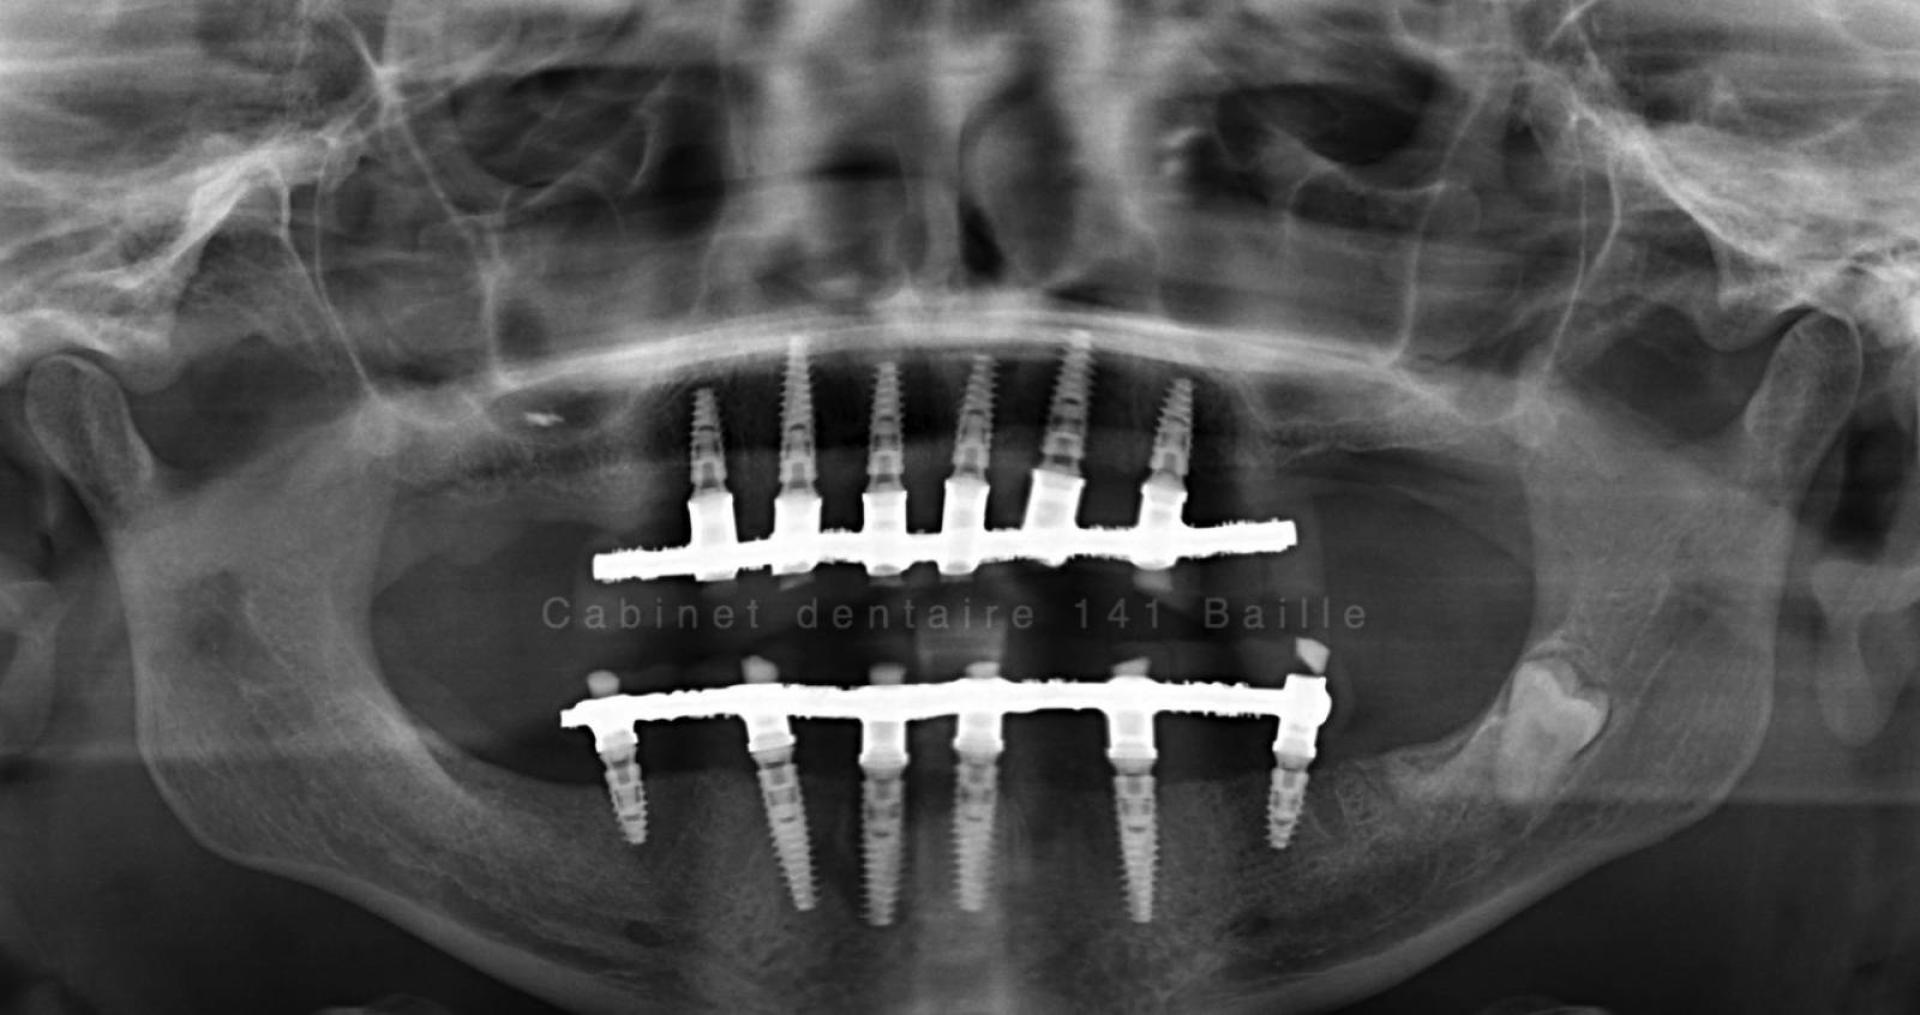

Nous sommes en mesure d'assurer la prise en charge de vos patients dans notre structure qui englobe la phase chirurgicale traitée naturellement en bloc opératoire stérile ,et sytème de traçabilité chirugicale aux normes hospitalières (Cycles prions à fractionnement de vide) ,pour tous les cas complexes intégrant implantations totales avec mise en charge immédiate.

Notre laboratoire intégré nous délivrera une prothèse immédiate qui permettra à votre patient de na pas avoir de gêne au niveau de sa vie sociale.

En général nous commençons à opérer le matin vers 9 h et la patient rentre chez lui vers 13h équipé d'une prothèse immédiate implanto- portée.